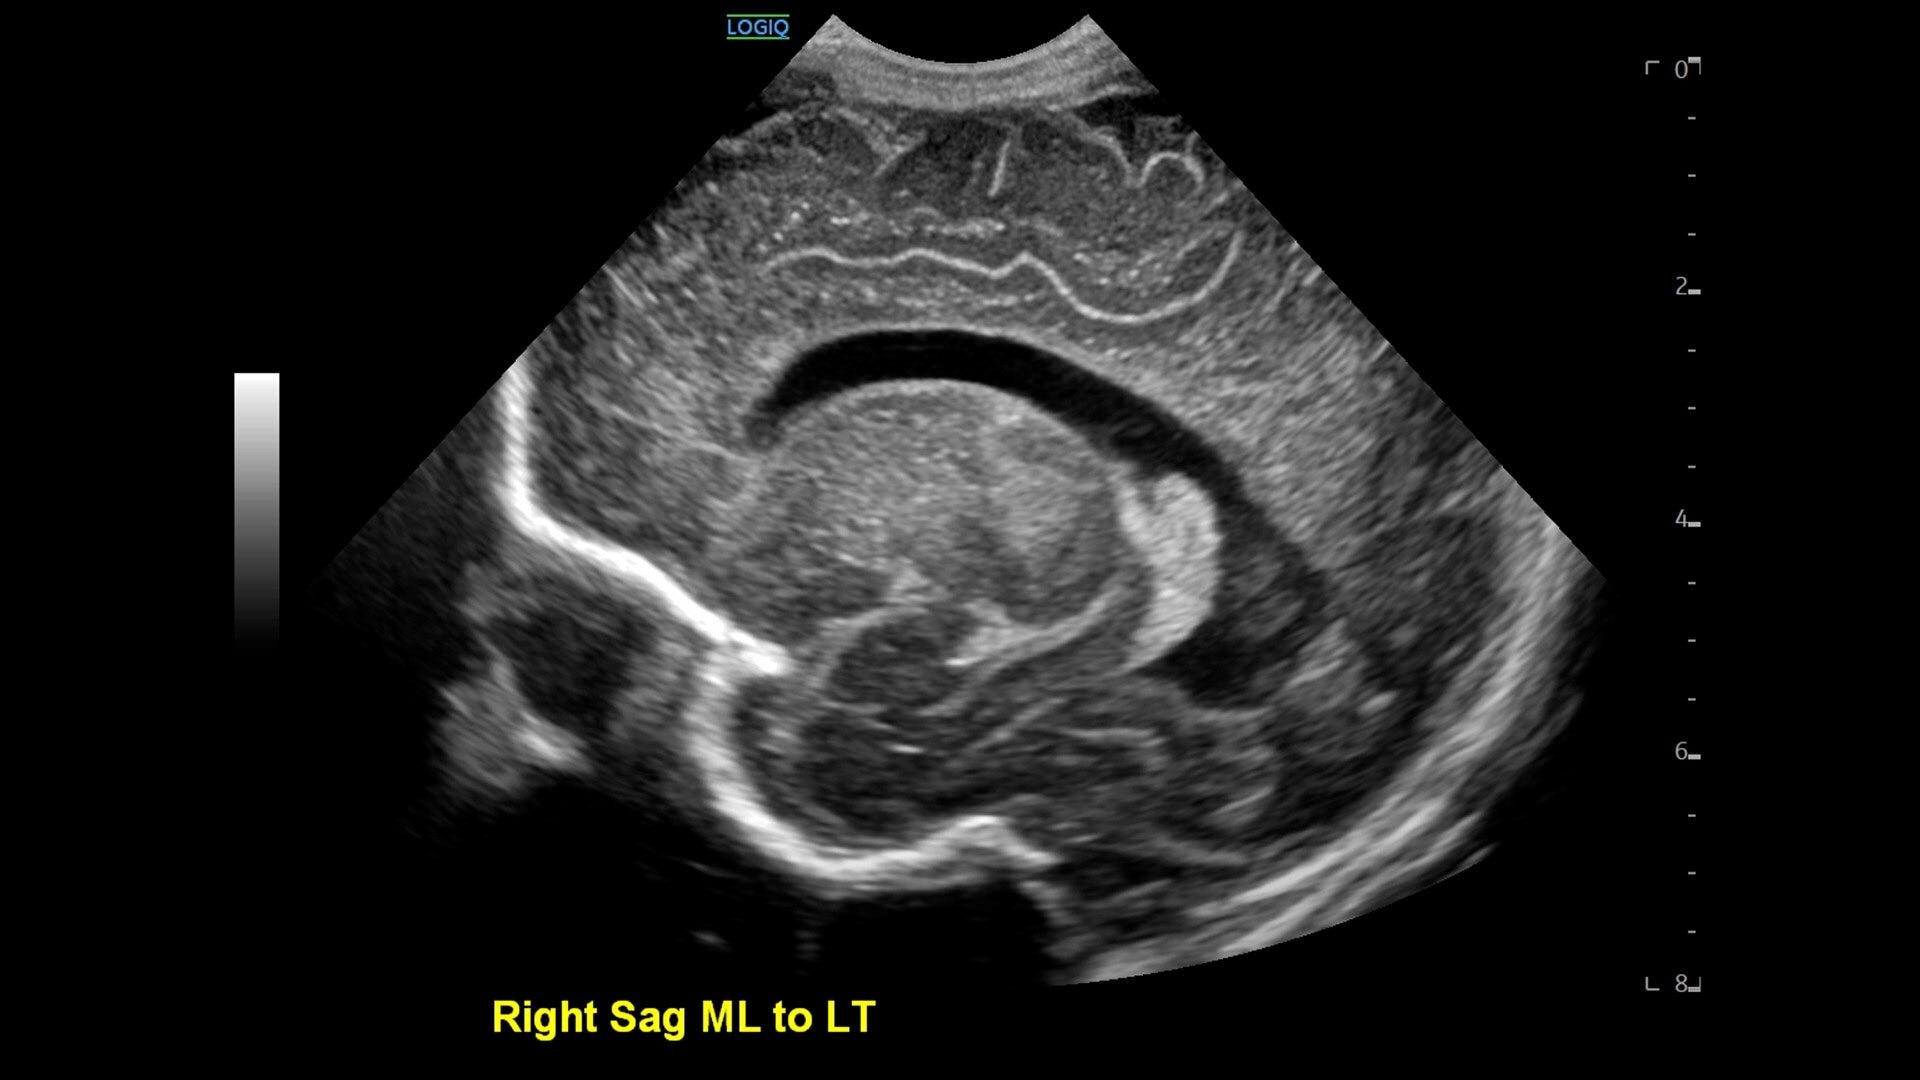

• cSound™ Architecture delivers exceptional clarity and resolution from near field to depth—with all pixels in focus

• Next‑level specialty and multi‑purpose probes—plus Pulsed Wave Doppler now available on the wireless Vscan Air™ CL —expand your clinical flexibility.